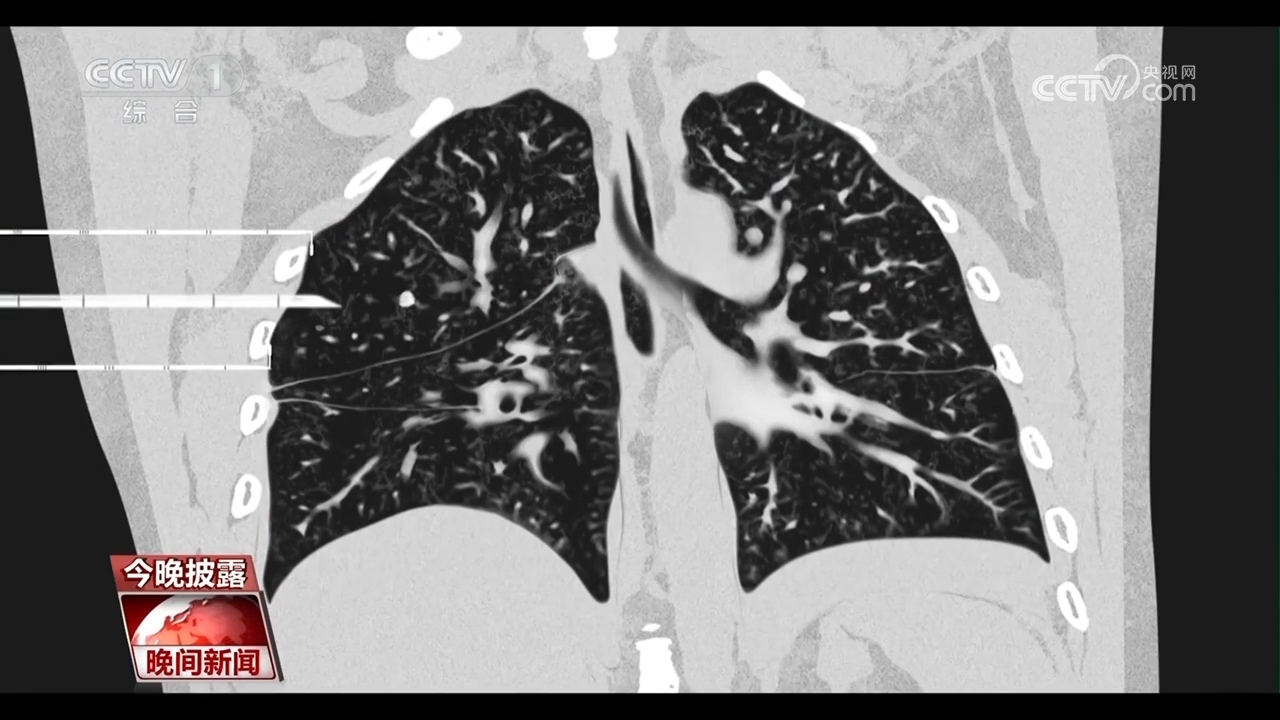

央視網消息:每年的11月是“全球肺癌關注月”。肺癌是我國發病率、死亡率最高的惡性腫瘤。隨著胸部CT的普及,越來越多的肺結節被篩查出來。眼下正值年底體檢高峰,一旦體檢發現肺結節,就意味著會有發展成肺癌的風險嗎?肺結節是否需要立刻手術呢?

專家介紹,2毫米以上的結節都能在CT上發現。肺結節不等于肺癌,而且絕大多數是良性的,胸部CT檢查初次發現肺結節,先不要恐慌,應根據醫生的建議定期復查,觀察肺結節的變化。

首都醫科大學宣武醫院胸外科首席專家 支修益:特別是復合肺結節直徑小于等于3厘米的磨玻璃結節,95%以上都是良性的,我們通過觀察它的大小、邊緣、密度的變化,來決定是否需要臨床干預,而小于6毫米的,我們根本就不干預,年度健康體檢就可以了。

雖然大部分的肺結節是良性的,不需要治療,但近些年來,40到50歲左右的肺癌患者明顯增多。由于肺癌的早期癥狀不明顯,70%到80%的患者確診時已是中晚期。因此,專家提醒,50歲以上的高危人群至少應做一次胸部CT進行肺癌的早期篩查。